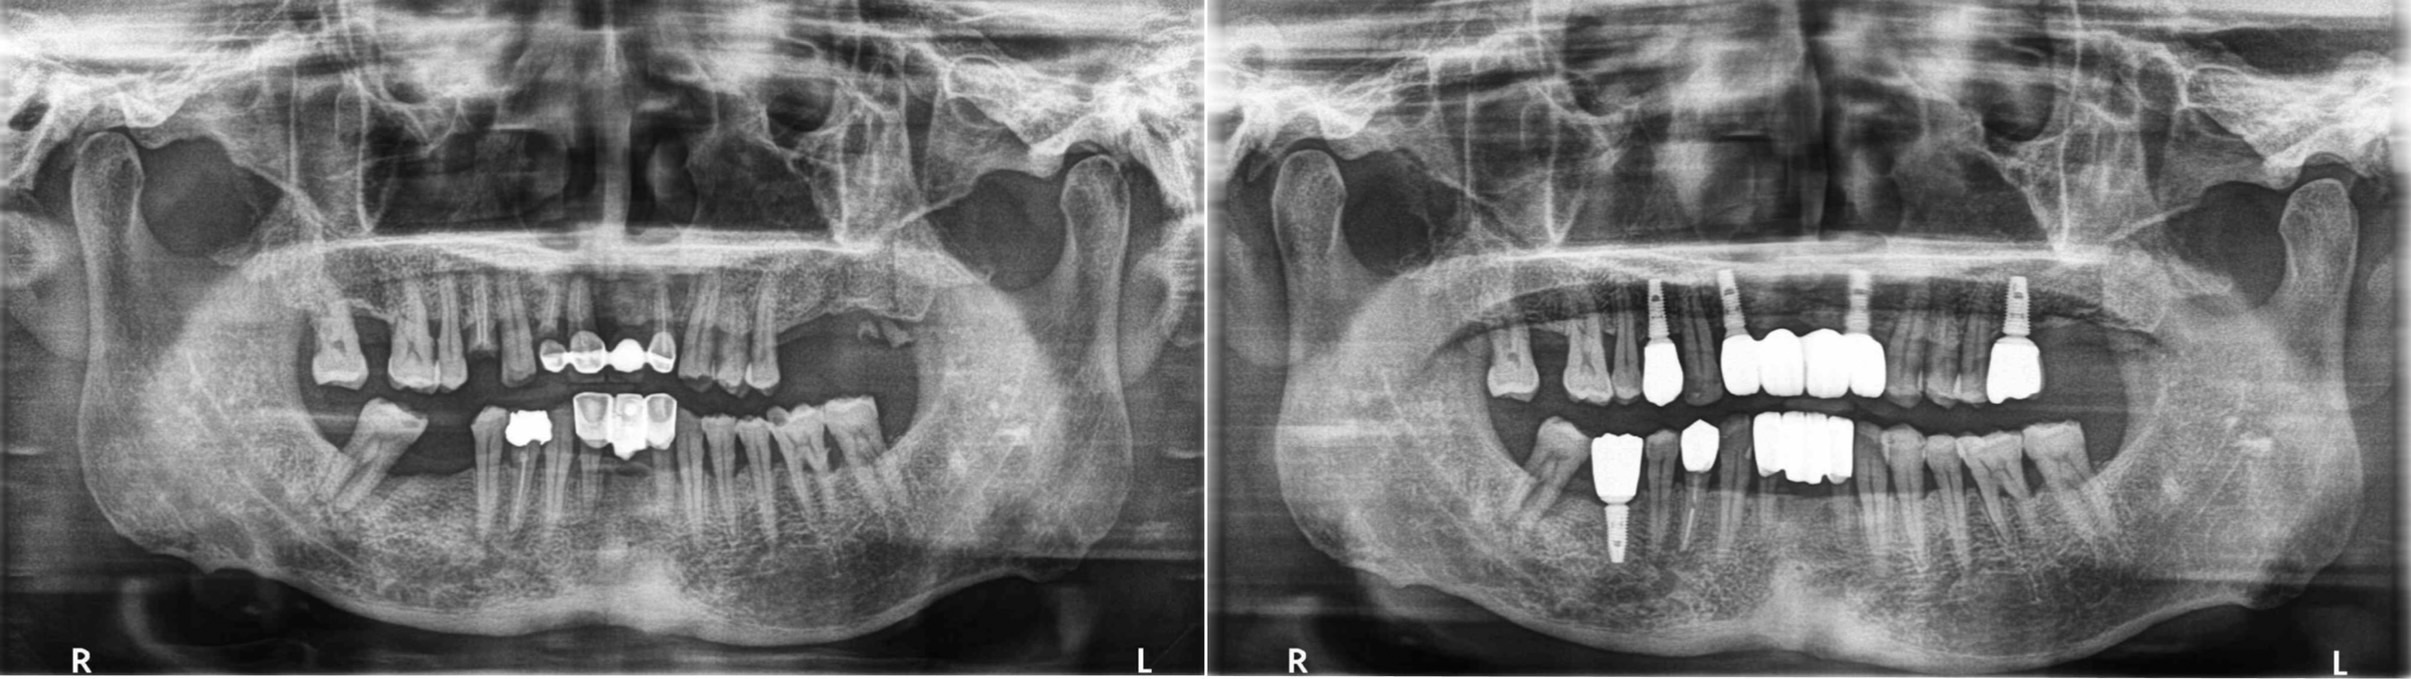

黃先生因為前牙假牙搖動無法進食而走進診間,經過電腦斷層和照相檢查判斷,告訴他現在牙齒會有現在的狀態有幾個原因,缺乏強而有力的大臼齒,後牙的咬合關係不好,進而造成其他前牙受力太大磨耗嚴重,最後前牙假牙崩壞。

了解之後,重建之路由此展開,處理的順序先從建立新的後牙咬合開始,利用三顆植牙和一顆假牙讓病人有穩定的後牙咬合後就差不多完成了,最後回到前牙,兩顆植牙乘載四顆假牙和下排換掉不美觀的假牙後完成病人的笑容

(左圖:治療前;右圖:治療後)